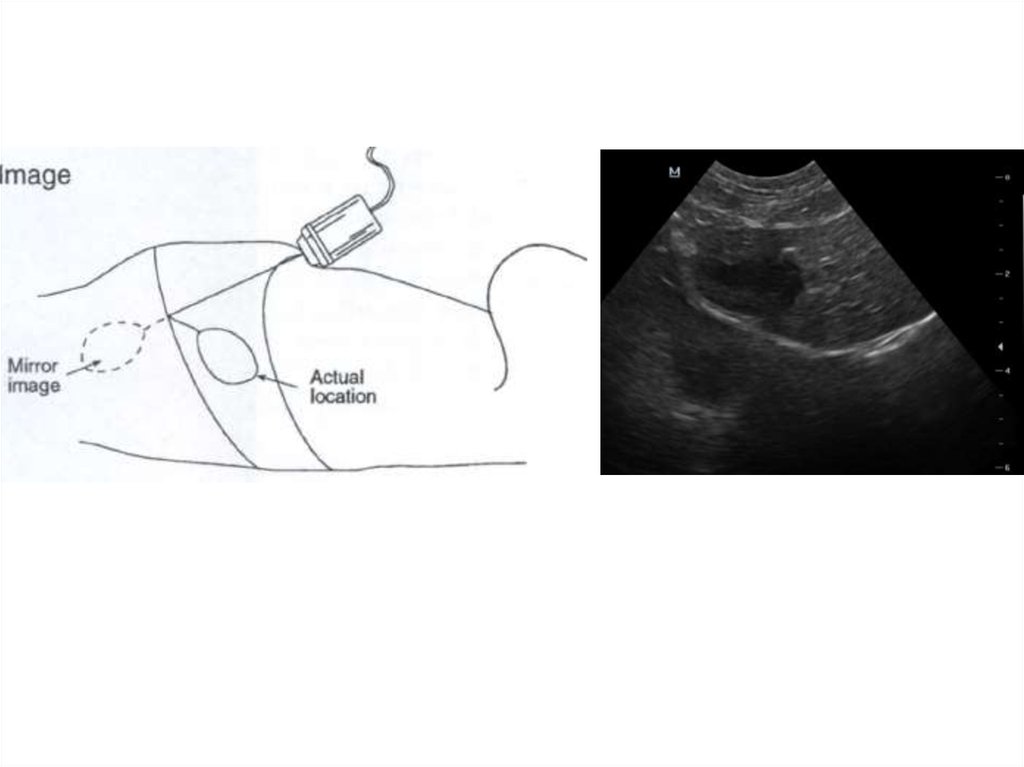

9. Зеркальное изображение

• Косо

ориентированные

поверхности

могут

отражать луч дистально

вместо того, чтобы вернуть

его к преобразователю

(угол падения равен углу

отражения)

• Объекты в направлении

луча отражают звуковой

луч,

а

затем

он

возвращается

к

преобразователю

• Отражаемый объект будет

показан

глубже

косой

поверхности отражателя

• Зеркальное отражение и

изображения

равноудалены от зеркала

• Форма

артефакта

искажается

при

искривлении зеркала

Маннион П., 2008

10. Диафрагма

• Печень и желчный

пузырь часто

регистрируются

краниальнее диафрагмы

• Артефакт отсутствует при

наличии плеврального

выпота, так как

отсутствует поверхность

(воздух в лёгких) с

высокой отражающей

способностью